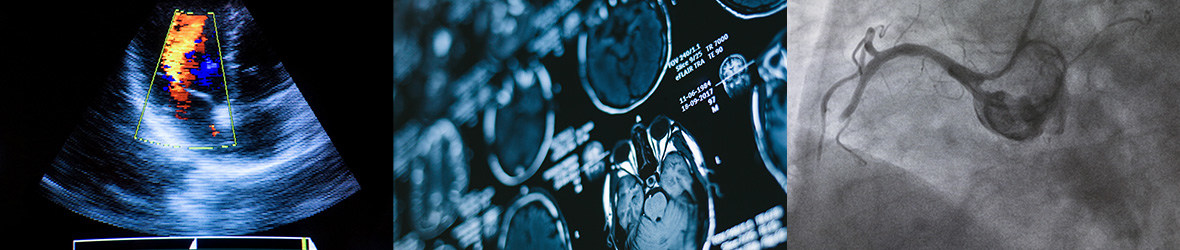

Medical scanners are used to produce pictures of the human body and are able to detect a lot of problems like bone fractures to tumors. Healthcare professionals utilise these images to evaluate and assist in the diagnosis of a disease state. In this article, we are going to go through information about common scans. This includes X-rays, a CAT scan, an MRI scan and ultrasound scans.

There are many different types of imaging scans that have various uses. Each type has its own purpose, and all of them are used extensively in modern medicine. We will discuss a few types here: